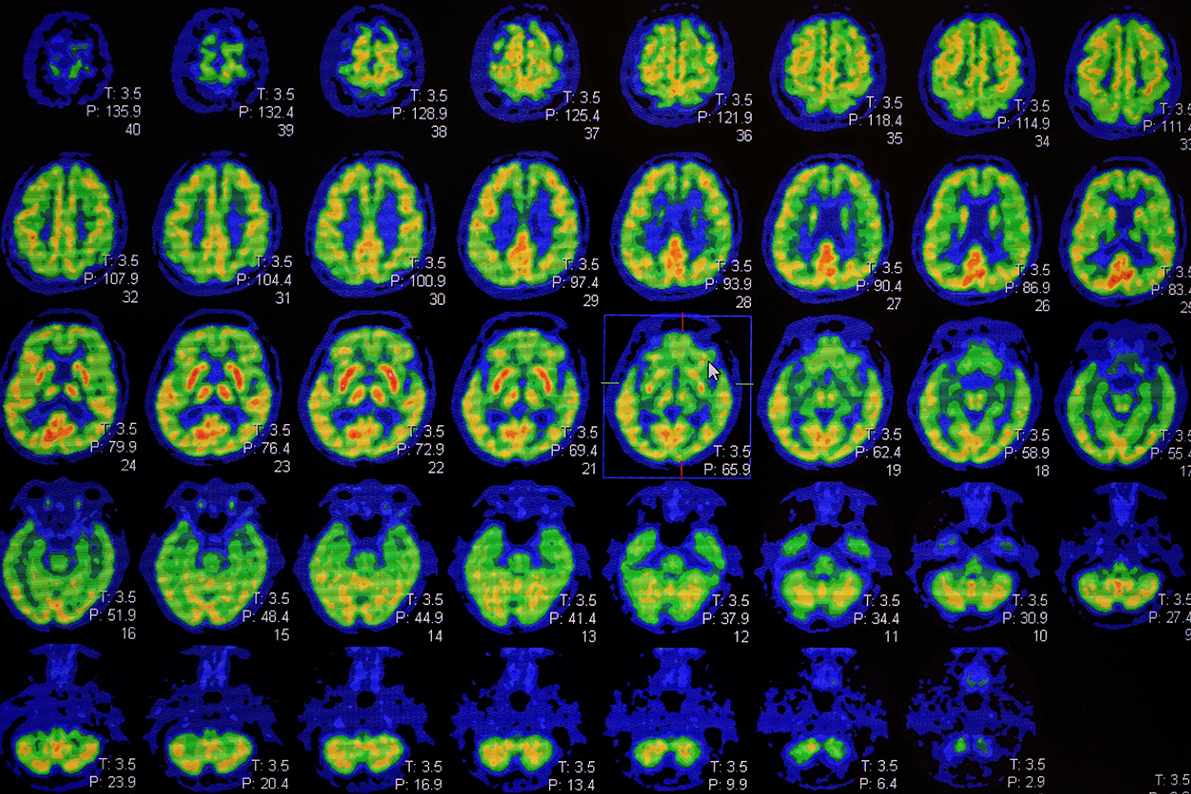

A multidisciplinary working group of 22 experts from eleven European scientific associations have joined forces to define recommendations for the effective and individualized use of biomarkers for the diagnosis of Alzheimer’s disease in memory clinics. Putting patients, instead of the disease or a test, at the center of doctors’ diagnostic considerations constitutes a turning point in the approaches currently applied.

Un groupe de travail multidisciplinaire composé de 22 expertes et experts de onze sociétés scientifiques européennes a uni ses forces pour définir des recommandations pour l’emploi efficace et individualisé des biomarqueurs pour le diagnostic de la maladie d'Alzheimer dans les cliniques de la mémoire. Mettre les patientes et les patients au centre des réflexions diagnostiques des médecins, au lieu de la maladie ou de l’examen, constitue un tournant par rapport aux approches en vigueur actuellement.